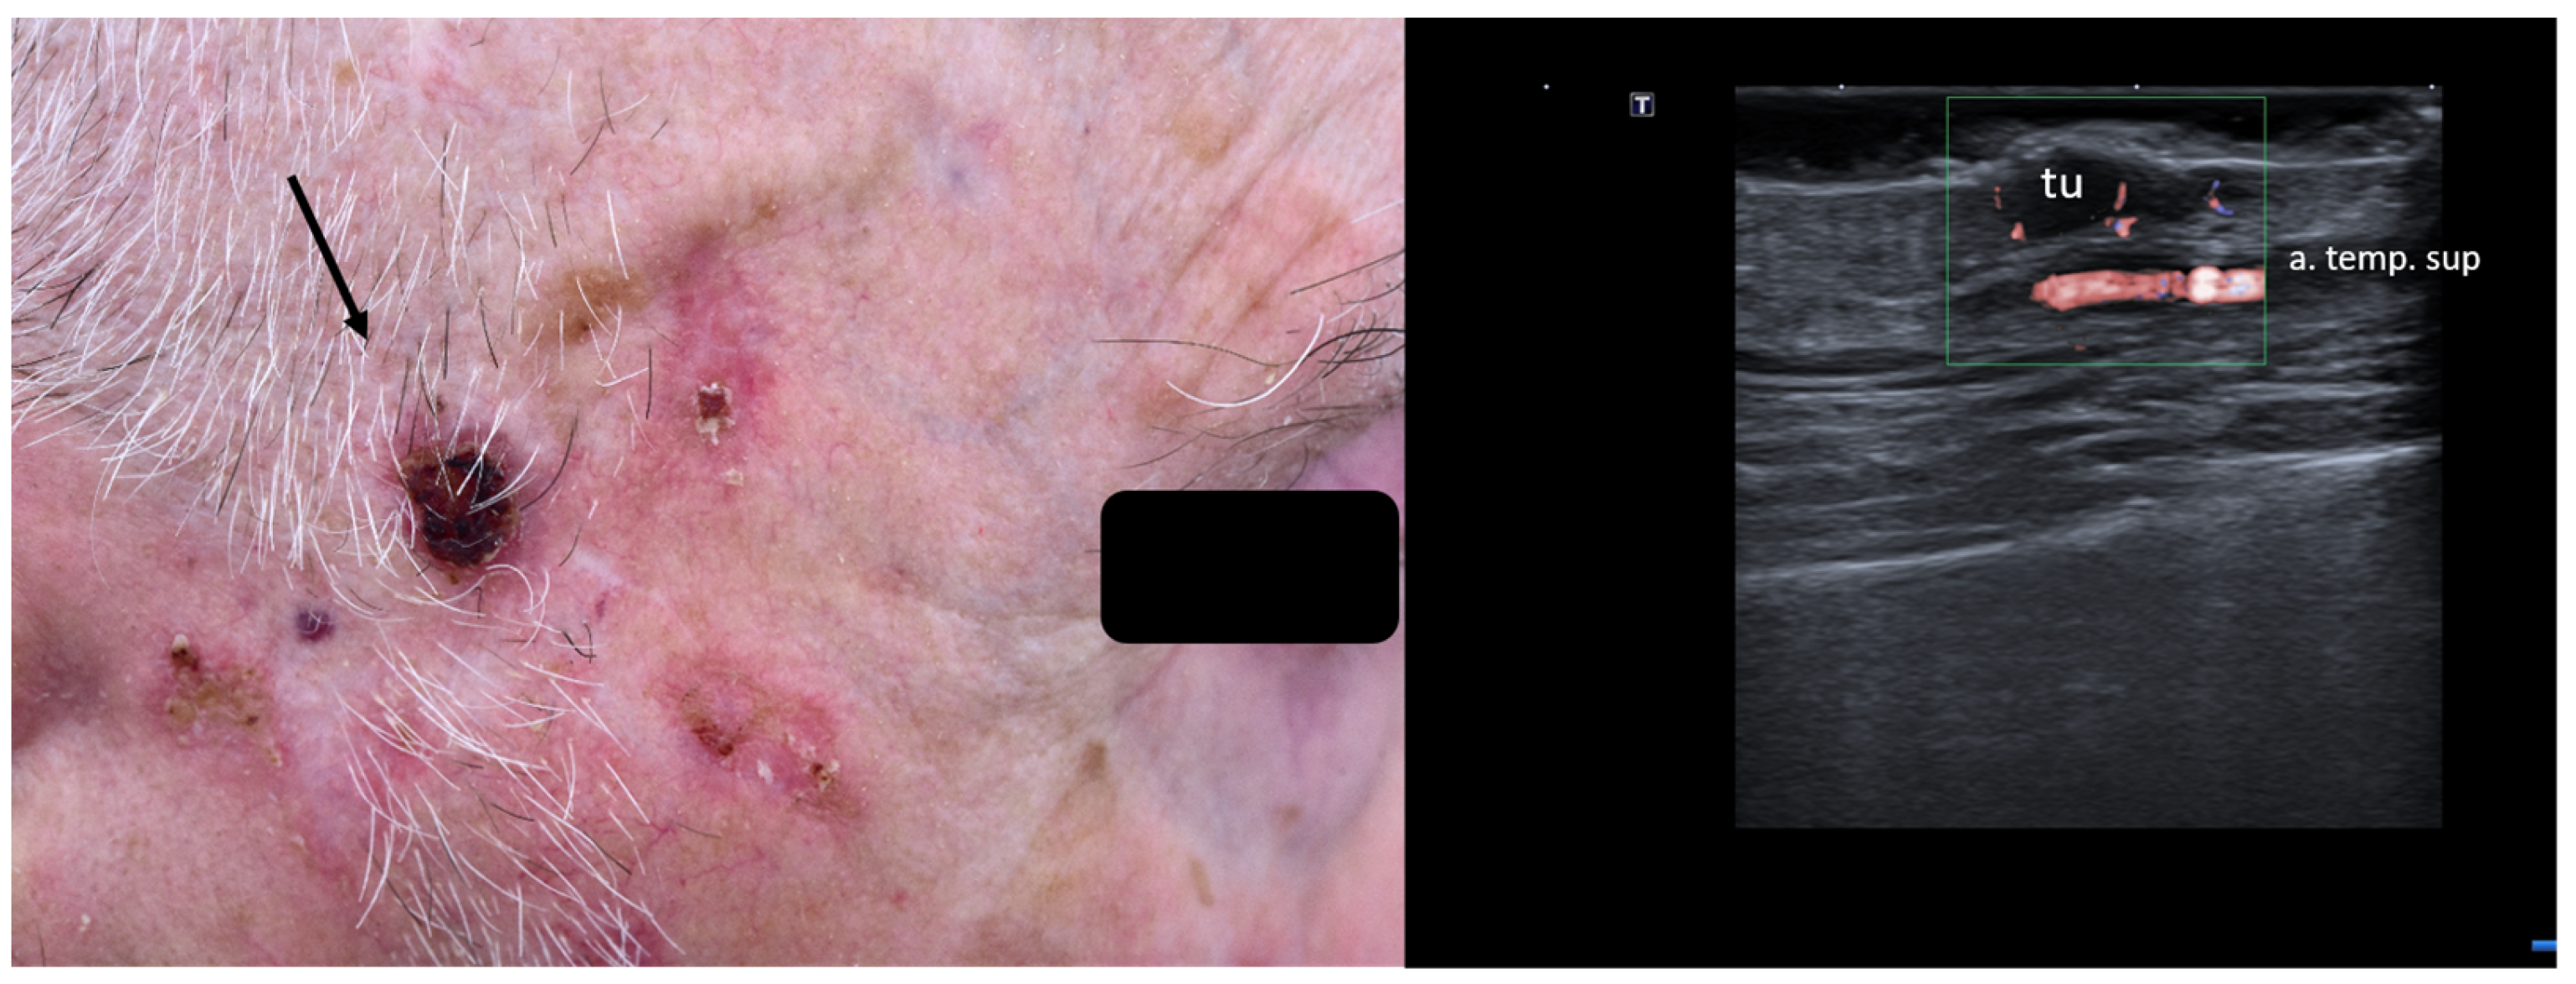

7. Choice of Surgical Approach

8. Preoperative Neuro-Vascular Mapping